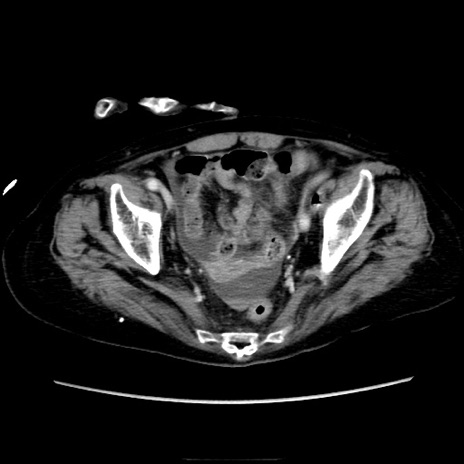

症例40(横断像)

横断像